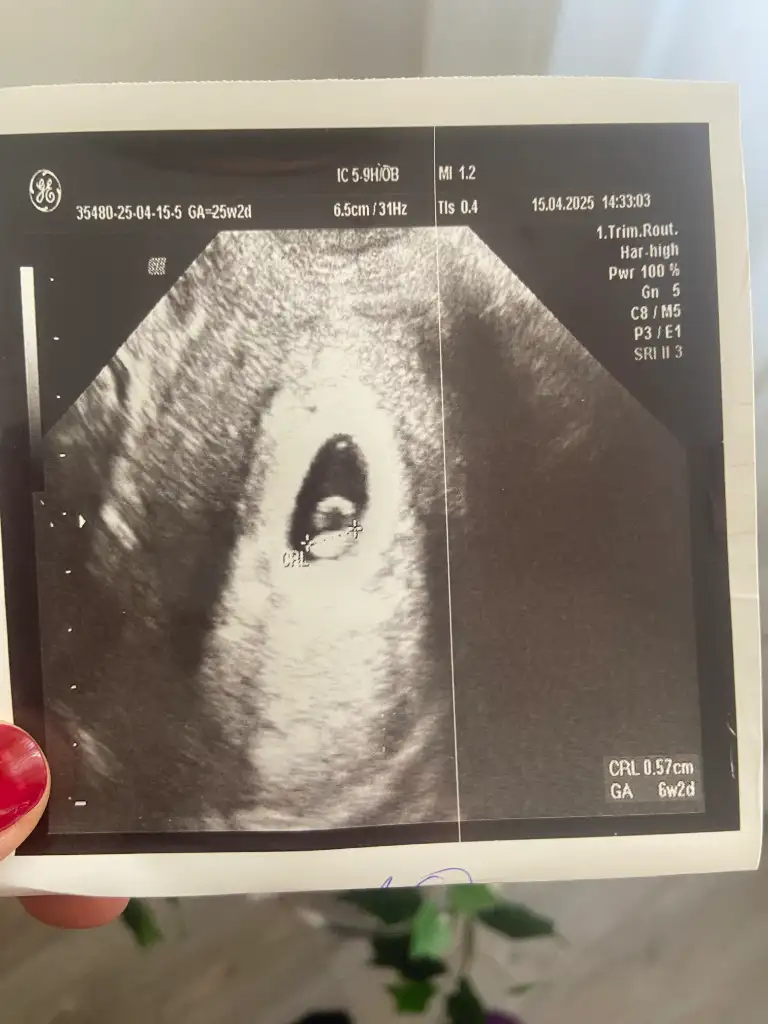

Çok geçmiş olsunMerhaba. Karından ultrasonla bakıldı. SAT’a göre 7+4’teyiz. Benim miniğime de bakar mısınız? Bir düşük tehdidi ile karşı karşıyaydık. 2 gün hastanede yatırdı beni yaramaz![]()